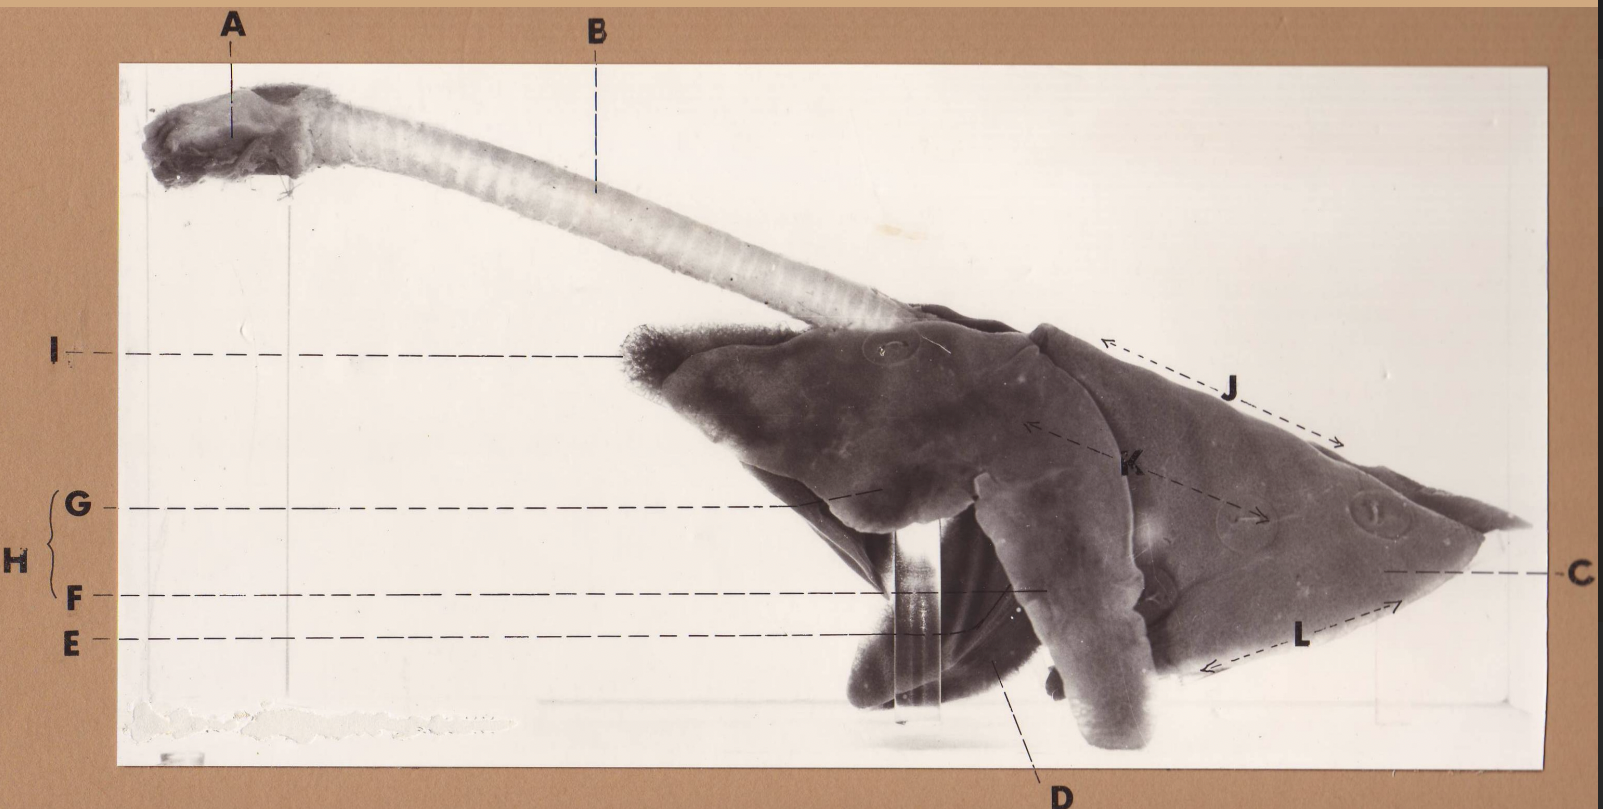

A

(cat larynx/trachea/lungs, L lateral)

larynx

B

(cat larynx/trachea/lungs, L lateral)

trachea

C

(cat larynx/trachea/lungs, L lateral)

caudal lobe

D

(cat larynx/trachea/lungs, L lateral)

middle lobe

E

(cat larynx/trachea/lungs, L lateral)

cardiac notch

F

(cat larynx/trachea/lungs, L lateral)

caudal segment, cranial lobe

G

(cat larynx/trachea/lungs, L lateral)

cranial segment, cranial lobe

H

(cat larynx/trachea/lungs, L lateral)

cranial lobe

I

(cat larynx/trachea/lungs, L lateral)

apex

J

(cat larynx/trachea/lungs, L lateral)

dorsal border

K

(cat larynx/trachea/lungs, L lateral)

costal surface

L

(cat larynx/trachea/lungs, L lateral)

basal border